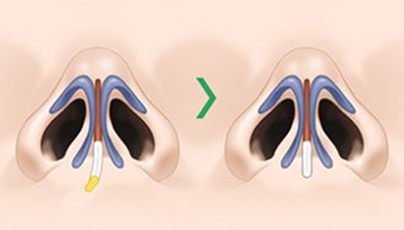

平平的正面和側面

矮鼻

在精確的診斷基礎上, 指定精準的手術計劃